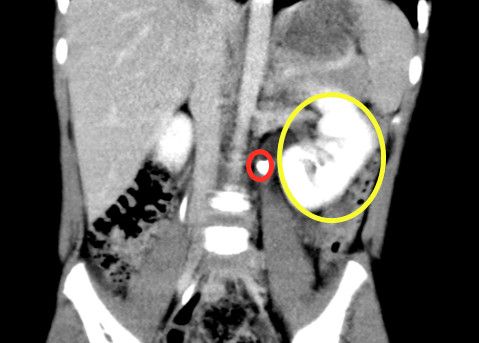

ct显示,左侧输尿管结石(红圈)、肾积水(黄圈)。

入院后完善CT检查显示,一颗蚕豆大小的结石堵在晨晨左侧肾盂与输尿管连接的地方,阻挡了尿液流经的通道,因此引发中度肾积水。必须尽快手术取出结石、疏通“下水道”。